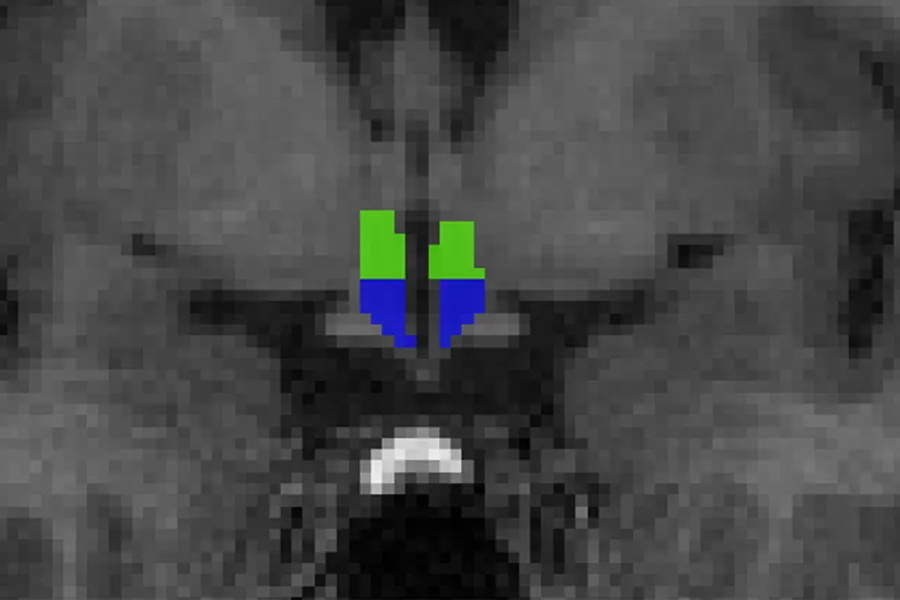

I en ny MR-studie av hjernen fra NevSom i samarbeid med NORMENT* studerte vi narkolepsi type 1 (NT1)-pasienter for å se om man kunne påvise volumendringer i hypothalamus. Hypothalamus er spesielt interessant hos NT1-pasienter som har tap/dysfunksjon av hypokretin-produserende nerveceller i dette området som man mener forårsaker mange av symptomene ved sykdommen. Vi fant overraskende resultater med større volum av hypothalamus hos pasienter sammenlignet med friske.

Vår studie er den første til å påvise større volum av hypothalamus, og særlig spesifikt i en region av hypothalamus kalt tubular-inferior.

En mulighet er at det er en sammenheng mellom våre funn og forandringer i antall nerveceller hos NT1-pasientene med økning i antall histaminerge nerveceller som er lokalisert i denne regionen. Tubular-inferior regionen har også blitt indikert som en mulig region av hypothalamus som kan ha gliose (hjernens arrvev) etter et eventuelt tap av hypokretin-produserende nerveceller hos NT1-pasientene Dette kan også potensielt være en del av forklaringen på forskjellene.